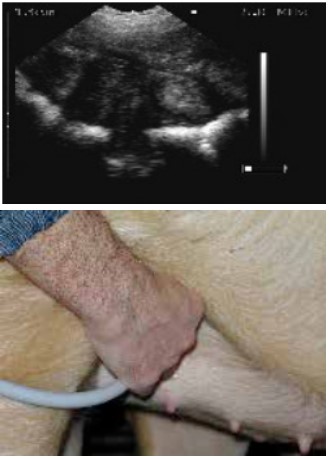

扫描配种第24天的母猪,大的胚胎囊可以很容易的看到。

Scans day 24. Large embryos bladders which are easy to see.

位置4的超声波图像.

Ultrasound image position 4

扫描仪的探头涂上耦合剂后置于腹股沟部。

The scanner head is applied gel and is placed in the groin.

缓慢地移动探头,直至出现胚胎清晰的图像。

lowly move the scanner head around until there is a clear picture of the fetus.